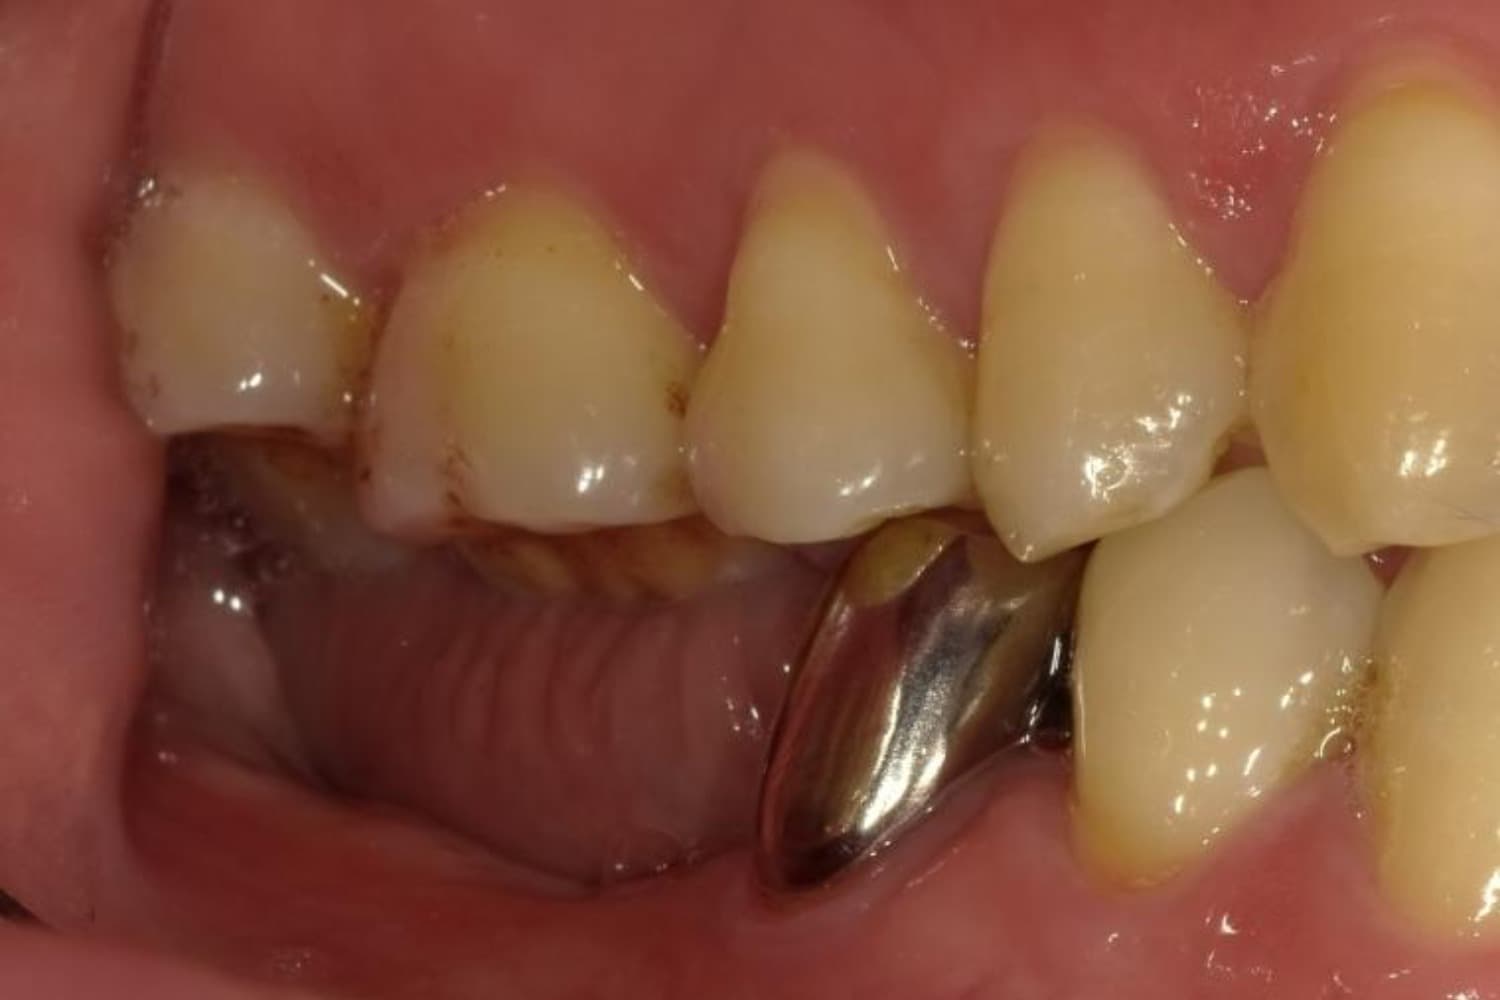

下顎大臼歯3本欠損症例

Before

After

左下第一大臼歯は保存が困難な状態であったため抜歯をおこないました。あわせて、ご来院時から欠損していた右下第一・第二大臼歯も含め、欠損部の補綴方法についてご説明し、インプラント治療を選択されました。

主訴

左下の第一大臼歯は別の医院で治療中でしたが、治療が思うように進まず、加えて他の箇所にも痛みが続いたことから、当院にご相談いただきました。

治療期間

10ヵ月

費用

140万円

副作用・リスク

インプラント治療は外科的な処置を伴い、多少の腫れや痛みが出ることがあります。 多くの場合は鎮痛薬で和らげることができます。